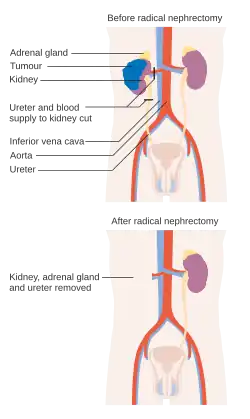

Before and after a radical nephrectomy | |

A nephrectomy is the surgical removal of a kidney, performed to treat a number of kidney diseases including kidney cancer. It is also done to remove a normal healthy kidney from a living or deceased donor, which is part of a kidney transplant procedure.[1]

The surgery is performed with the patient under general anesthesia. A kidney can be removed through an open incision or by laparoscopic surgery. For the open procedure, the surgeon makes an incision in the side of the abdomen to reach the kidney. Depending on circumstances, the incision can also be made midline. The ureter and blood vessels are disconnected, and the kidney is then removed. The laparoscopic approach utilizes three or four small (5–10 mm) cuts in the abdominal and flank area. The kidney is completely detached inside the body and then placed in a bag. One of the incisions is then expanded to remove the kidney for cancer operations. If the kidney is being removed for other causes, it can be morcellated and removed through the small incisions. Recently, this procedure is performed through a single incision in the patient's navel. This advanced technique is called single port laparoscopy.

A total nephrectomy is the removal of at least the entire kidney, whereas a 'radical nephrectomy' also includes at least some perinephric fat, possibly including Gerota's fascia, and usually also the ipsilateral adrenal gland.[10]